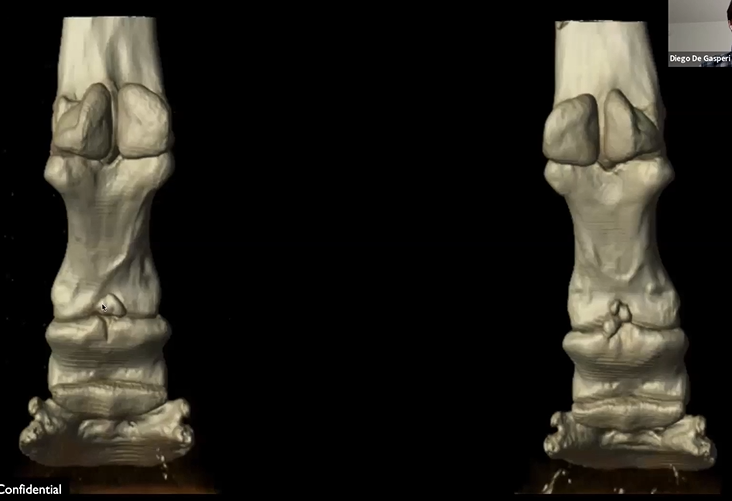

Read MoreCT images show bilateral fragmentation of the proximal palmar articular surface of the middle phalanx. They surgical removed multiple fragments in the right forelimb. Watch the video to view 3D reconstructions. Featured: Dr. Diego De Gasperi, University of Wisconsin-Madison